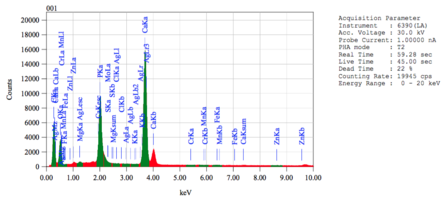

Химический состав минерализованного губчатого порошка.pdf

3. Полный точный химический состав материалов